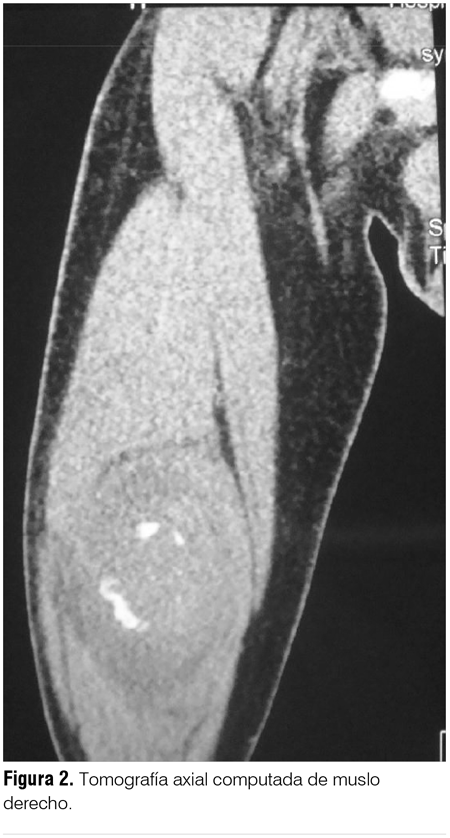

La ecografía y la tomografía axial computada (TAC) de muslo derecho mostraron una imagen groseramente ovalada, bien delimitada, heterogénea, con calcificaciones periféricas sin vascularización valorada por Doppler color (figura 2).